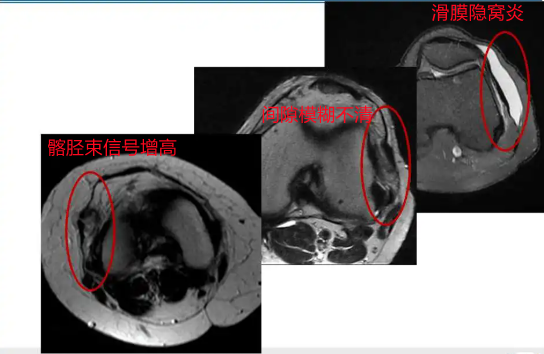

影像学表现

1 T2WI PD 序列上可以显示靠近股骨外侧髁与髂胫束之间的信号增高,边界不清,外侧滑膜增厚;

2 髂胫束靠近股骨外侧髁水平出现增厚改变,部分严重患者可以出现连续性中断;3 髂胫束表面或深部信号明显增高;4 可伴股骨外侧髁反应性骨髓水肿